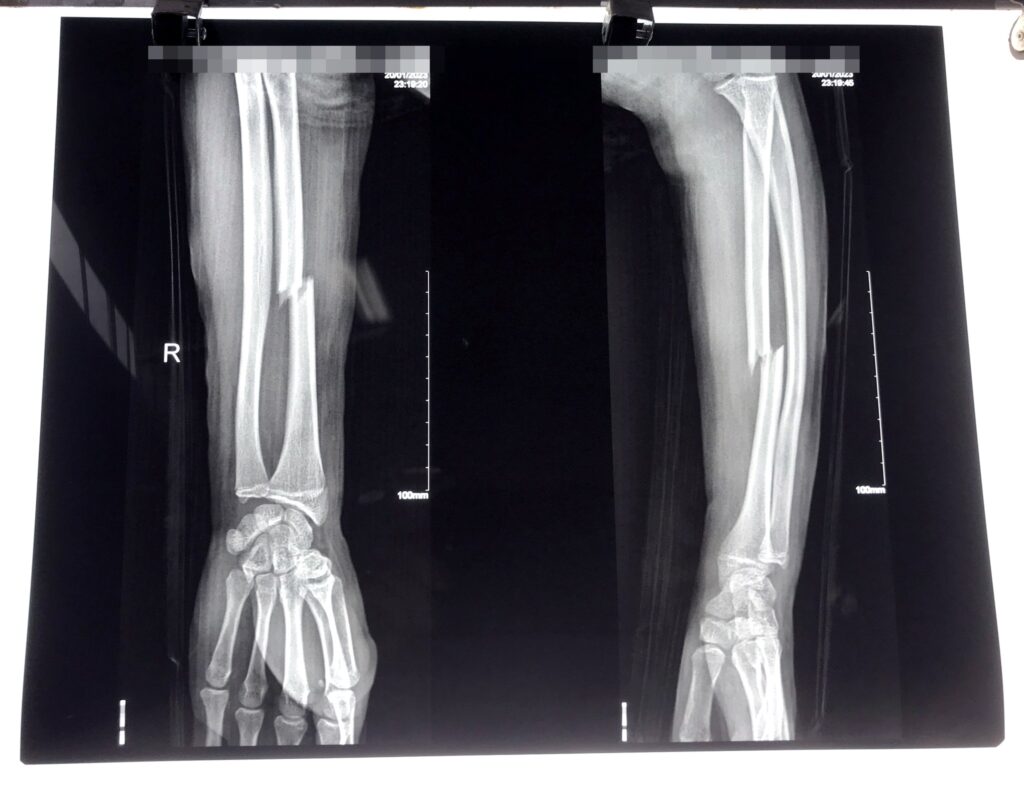

Hoàn thành ca phẫu thuật xương cho bệnh nhân 17 tuổi gãy giữa xương quay phải do tai nạn giao thông.